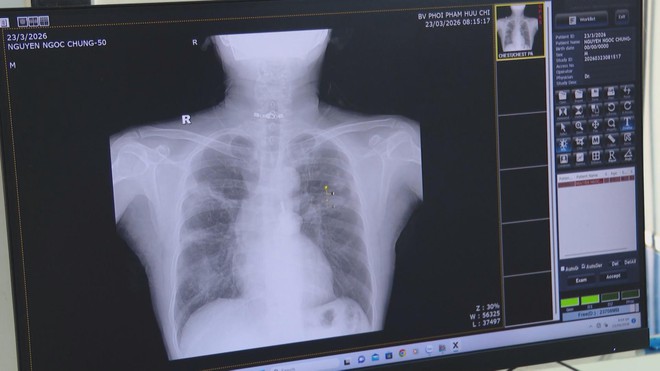

Theo Bác sĩ Lê Hữu Bình - Phó Giám đốc Bệnh viện Phổi Phạm Hữu Chí, TP. Hồ Chí Minh: "Điều trị dứt khỏi bệnh lao thì ta phải tuân thủ theo 5 nguyên tắc điều trị: Điều trị đúng liều, đúng thuốc, phối hợp thuốc, đủ thời gian và phải kiểm soát tốt theo chương trình chống lao quốc gia. Nếu trong gia đình có bệnh nhân lao thì chính bệnh nhân phải tự giác đeo khẩu trang, cách ly người nhà mình nên động viên, quan tâm người bệnh nhưng vẫn giữ khoảng cách, đeo khẩu trang, hạn chế lại gần trong 2 tuần đầu mình cũng phải đi xét nghiệm lao tiềm ẩn".